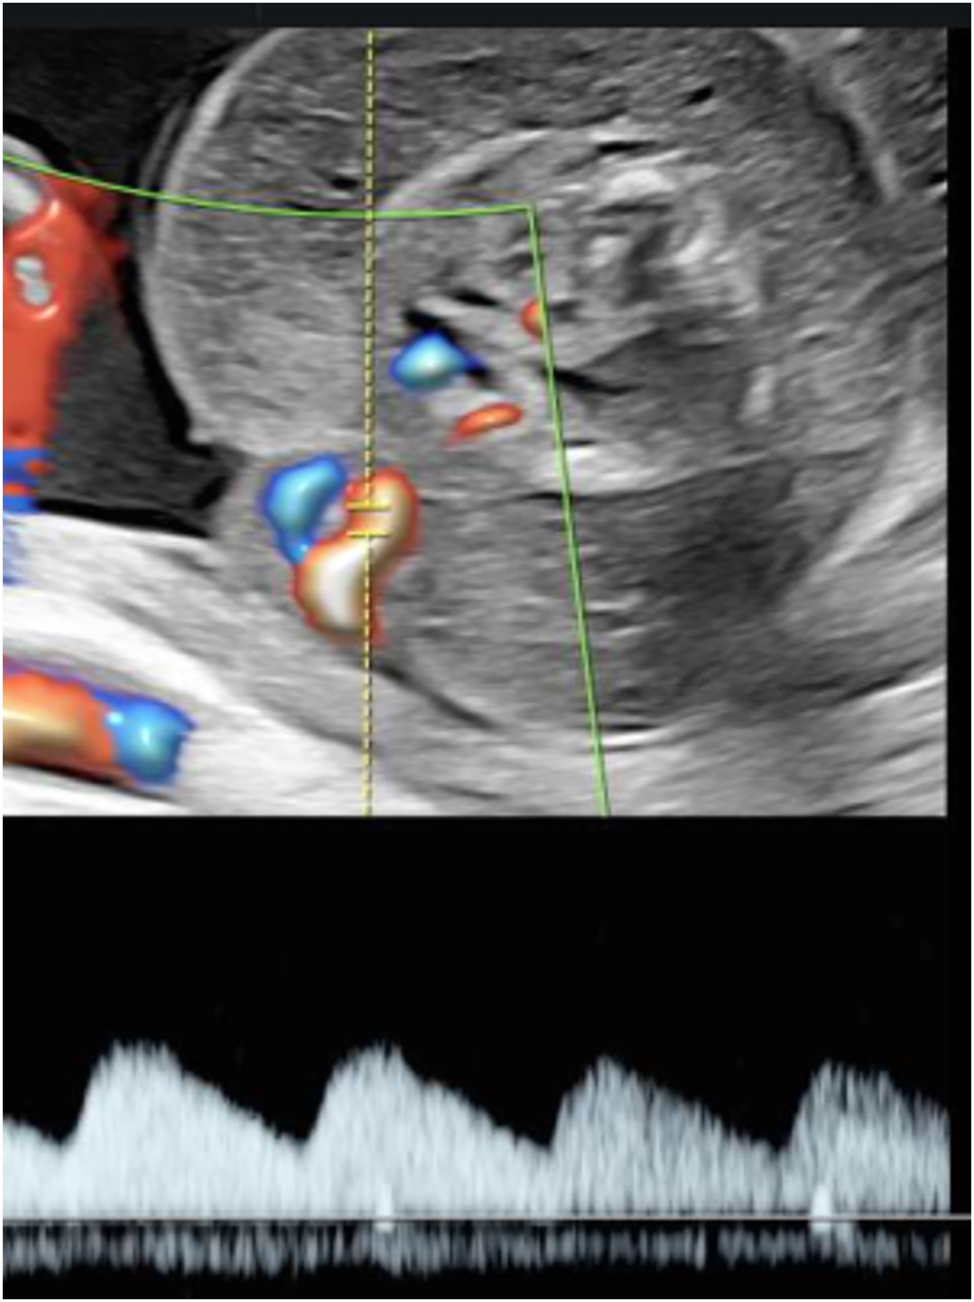

Type 3 sFGR presents with unique flow pattern and is often only recognizable when the umbilical Doppler flow is observed over a longer period and the measurement is taken at close proximity to the placental cord insertion site (Figure 7). The typical alternation of positive phases with AREDF usually occurs cyclically and indicates the presence of a large arterioarterial anastomosis, which transfers the systolic flow pattern of the larger twin to the umbilical artery of the smaller twin. In type 3, the placental supply area of the FGR twin is typically significantly smaller than that of its co-twin. Survival is primarily ensured by large interfetal anastomoses and the resulting blood exchange [8]. This subgroup is associated with a 10–20 % risk of IUFD of the growth-restricted fetus, which, unlike type 2, is not preceded by the typical sequential cascade of decompensation and is therefore unpredictable and can even occur in situations with apparently stable ultrasound findings. Due to the large AA anastomoses, there is also a significantly increased risk of up to 20 % of neurological sequelae in the surviving co-twin [77], 78]. Depending on the clinical findings, technical possibilities, and parental wishes, an expectant approach or a prenatal intervention in the form of laser ablation or selective feticide may be chosen [75], 76], 79]. The average gestational age at birth is between 29 and 34 weeks [73].

Umbilical artery Doppler flow pattern in sFGR type 3 at 22 + 6 weeks of gestation. Demonstration of intermittent end-diastolic positive flow, absent flow and negative flow.